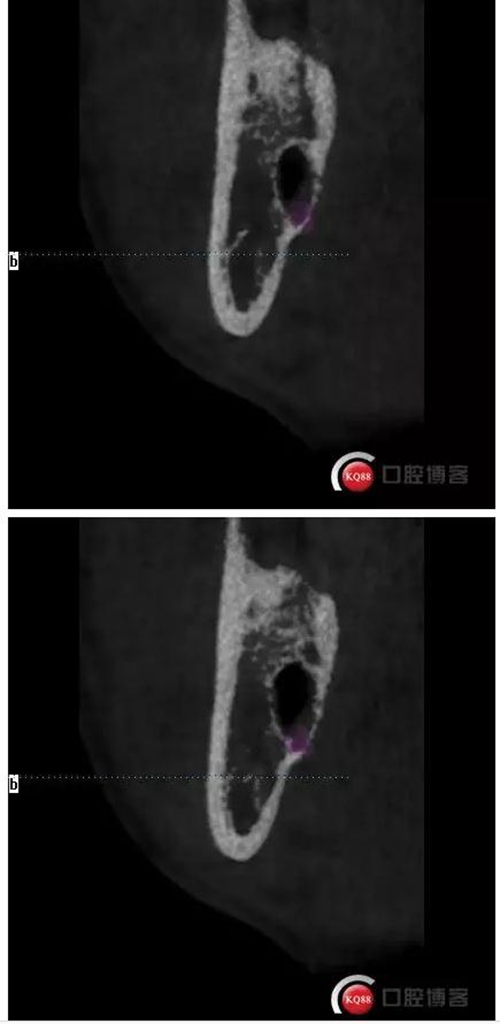

下面CBCT,可以看到兩個(gè)牙根的根尖三分之一在神經(jīng)管里面。

CBCT神經(jīng)管標(biāo)線,可以看到標(biāo)線不能連續(xù),中間被阻斷。